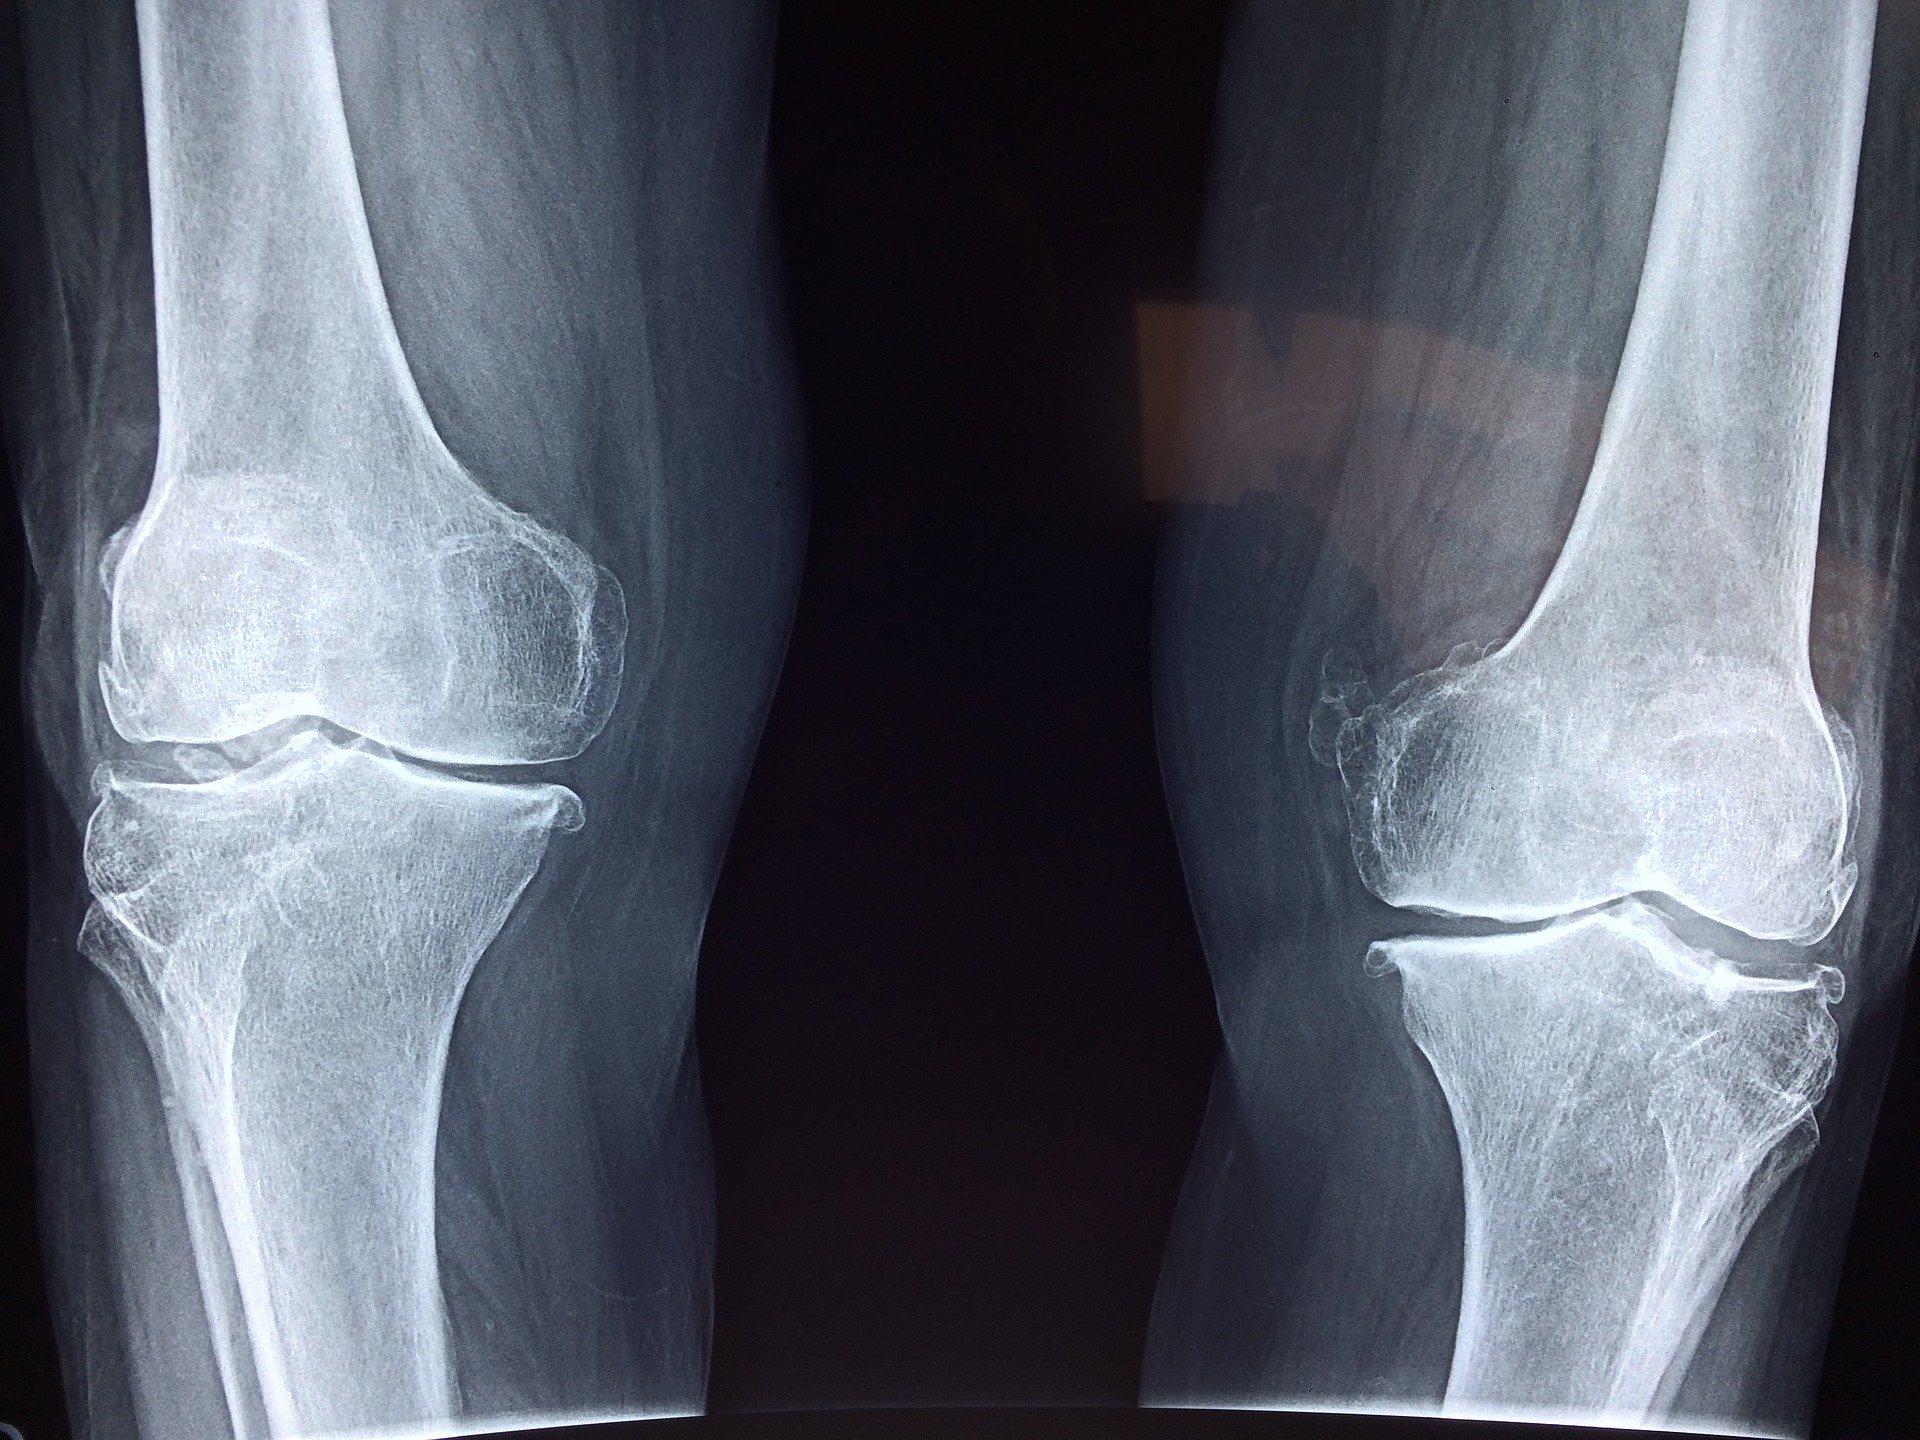

강력한 뼈

골다공증은 나이가 들어감에 따라 뼈가 약해지는 것입니다. 근력 운동은 이를 예방하거나 악화되는 것을 방지하는 데 도움이 된답니다. 운동은 세포 중에도 뼈를 생성하는 세포를 형성 합니다. 엉덩이, 척추 및 손목은 근력 운동의 가장 큰 이점을 얻을 수 있습니다. 또한 골다공증의 영향을 가장 많이 받는 곳이기도 합니다.

근력 운동이나 무게저항 운동을 하면 관절이 정상적으로 움직일 수 있습니다. 뼈 주위에 근육을 형성하면 관절에 윤활유를 공급하고 부기를 완화하며 뼈가 손실되는데 늦추는 데 도움이 됩니다. 이것은 관절염과 같은 상태에서 뻣뻣함이 있는 경우 특히 유용합니다.